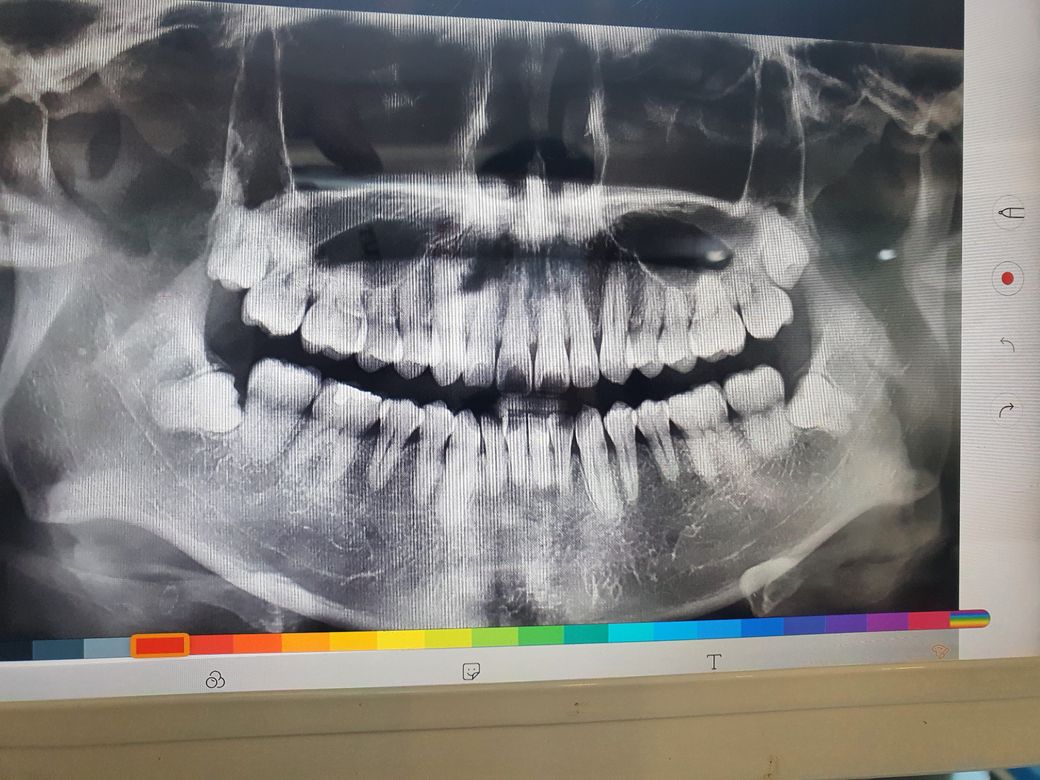

아래 사랑니 빼러갈때 찍은 사진입니다.(1달전)

아래쪽 2개는 제거가 완료된 상태고 위에 2개가 남았는데 상악동쪽에 가깝게 위치하고 있어서 나중에 빼려고 했습니다.

어렸을때 교정을 한 상태라서 치아 공간이 많이 없습니다. 현재 불편한건 전혀없고 나중에 문제가 될까 걱정이 좀됩니다.

일반의의 상식 수준에서 보자면 말씀하신 양쪽 사랑니의 경우 발치가 가능해 보입니다.